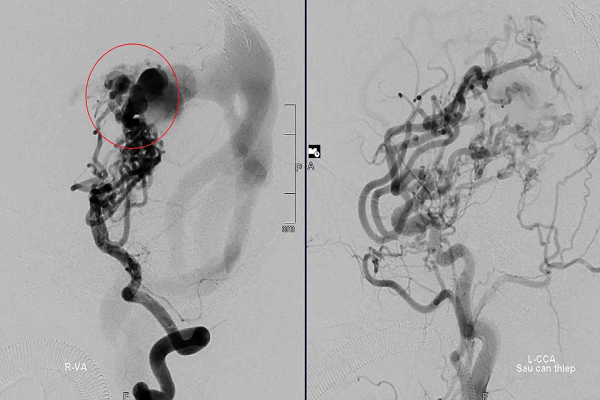

Các bác sĩ phát hiện trong não của bé tồn tại một khối dị dạng mạch máu não bẩm sinh với cấu trúc cực kỳ phức tạp, nhiều động mạch nuôi giao nhau và lưu lượng máu chảy qua rất lớn. Nếu khối dị dạng này vỡ, bé có thể tử vong.

Các chuyên gia đầu ngành trong, ngoài nước đã hội chẩn và nhận định đây là trường hợp dị dạng mạch máu não khá lớn, phức tạp, rất khó để can thiệp.

Trong suốt 10 năm, D. đã trải qua 8 lần can thiệp. Mỗi lần bước vào phòng mổ là một lần gia đình "nín thở", các bác sĩ đấu trí từng mm, còn số phận thì “đánh cược” với thời gian.